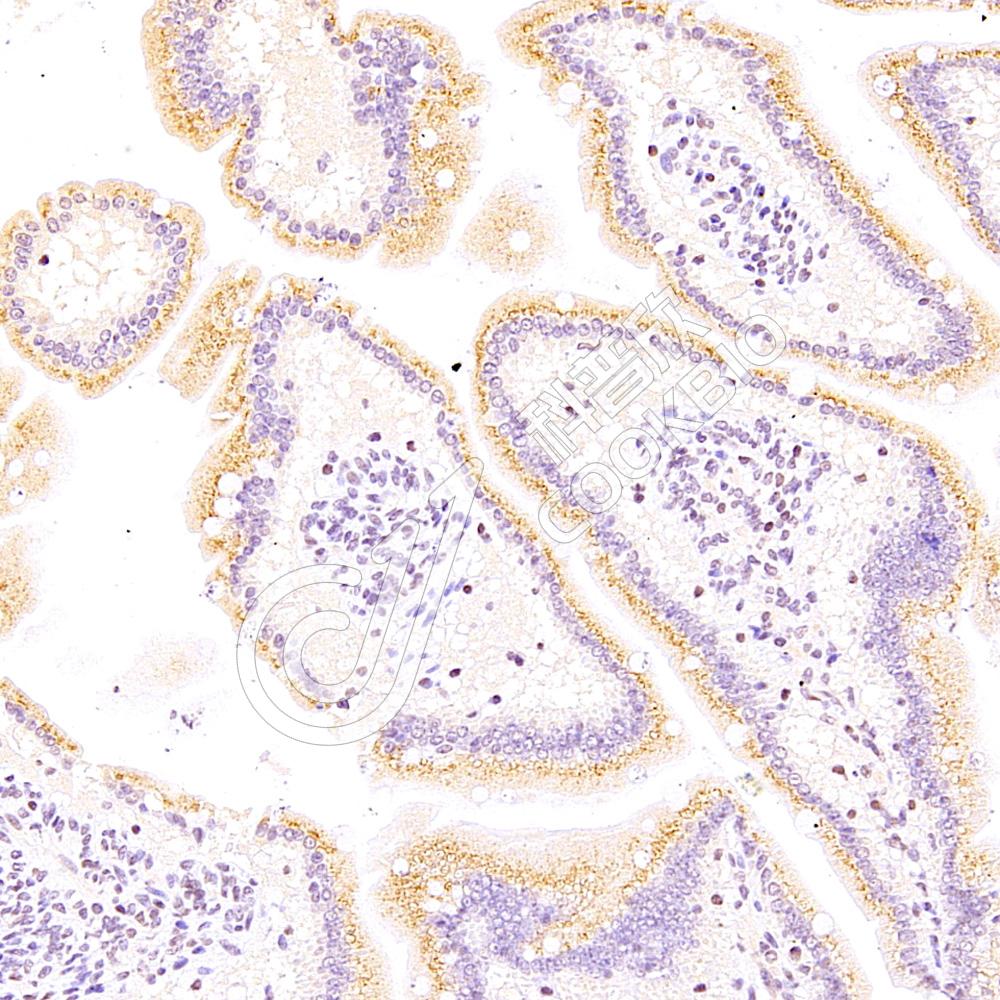

IHC检测TRPC3蛋白(货号 K1333621).

样品: 小鼠脑, 4%多聚甲醛 (货号KSG1101) 固定12-24小时.

抗原修复: 柠檬酸抗原修复液(干粉, pH 6.0) (KSG1201), 98℃, 20分钟.

—抗: 1: 2500稀释, 4℃ 孵育过夜.

二抗: S-vision免疫组化多聚二抗(山羊抗兔),即用型 (货号KB3906), 室温孵育20分钟.

样品: 大鼠脑, 4%多聚甲醛 (货号KSG1101) 固定12-24小时.